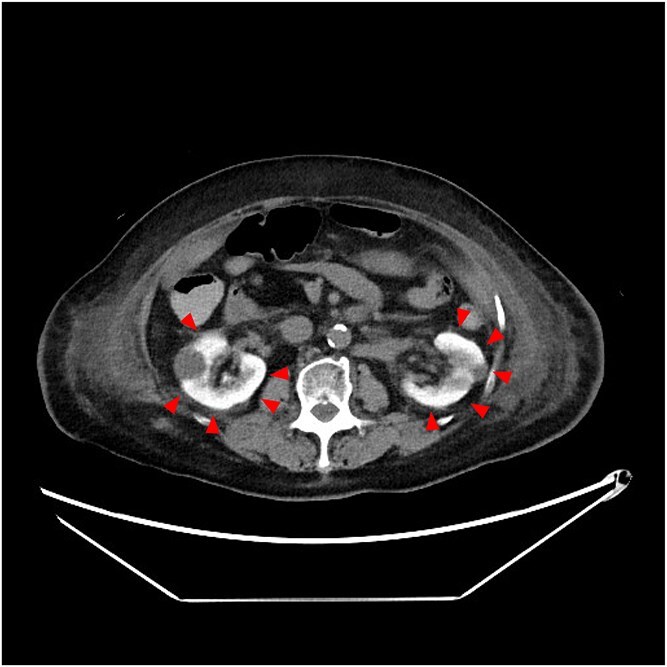

亮肾:经皮冠状动脉介入治疗后造影剂肾病的征象。

Bright kidney: a sign of contrast induced nephropathy after percutaneous coronary intervention.